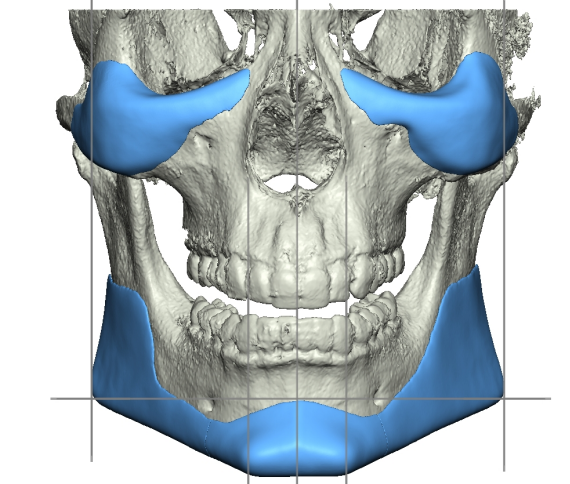

Recently got this implant design from Dr. Y for custom mandible (jaw & chin) and malar / cheekbones with infraorbital rims.

Interested in thoughts.